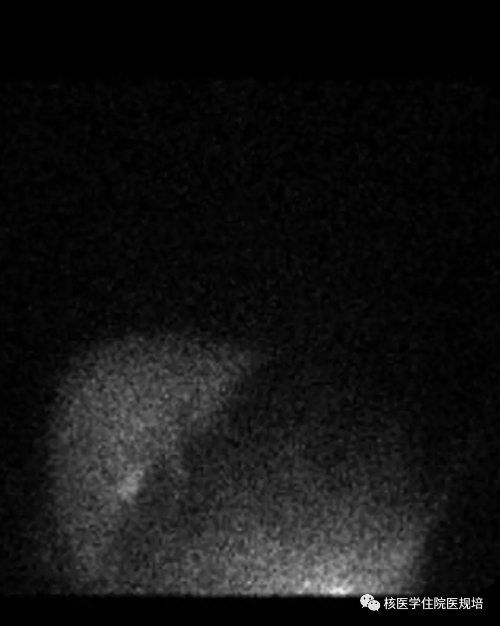

经直肠注入99mTc-MIBI 20mci60分钟后,行心脏至肝脏前位平面静态显像(图1),结果显示:心脏显影基本清晰,肝脏形态欠规整,左叶相对增大,肝内示踪剂分布基本均匀,脾脏增大并可见显影。

分别勾画心脏和肝脏ROI,根据公式计算:

心肝血流比值(H/L):0.97(参考值<0.53

门体分流指数(SI):0.49(参考值<0.33

门静脉压力(PVP):3.74kPa

核素心/肝血流比值测定法的原理:直肠内注入99mTc-MIBI后被直肠粘膜吸收后,正常情况下通过直肠上静脉至肠系膜下静脉进入门静脉而运行至肝脏,被肝脏处理之后再经肝静脉汇入下腔静脉,因此99mTc-MIBI绝大部分首先被肝脏摄取,肝脏显影清晰,而心影不显影或显影浅淡(图2)。当门静脉压力增高时,由于位于直肠下段粘膜下层的吻合支,即直肠静脉丛开放,使部分显像剂绕过肝脏而直接回心,从而使心脏较早的显影清晰,心肌摄取显像剂明显增高(图1),且对显像剂的摄取量与分流程度成正比。